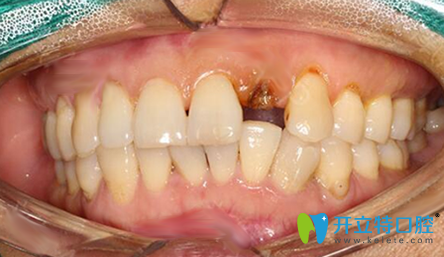

缺失一顆門牙:

剛開始牙齒疼的時(shí)候沒在意,等到后來就直接壞了。門牙是裝點(diǎn)門面的,一壞,我都不敢笑啦,也不知道是心里作用還是怎么的,我竟感覺旁邊的門牙也有活動(dòng)的跡象,所以聽朋友說貝臣口腔能做種植牙,也正好有活動(dòng),我就趕緊行動(dòng)啦。

到接診的是羅維明院長(zhǎng)!羅院長(zhǎng)在了解了我的情況后,對(duì)口腔全景ct深度分析,說我剩下的牙齒殘根已經(jīng)無法再滿足做普通的牙齒美學(xué)修復(fù),只有拔除剩下的殘根,做種植牙才是的牙齒修復(fù)的方式。

拔出剩余的殘根之后,就直接開始做種植牙了,這是護(hù)士幫忙拍的照片,因?yàn)榇蛄寺樗?,種植牙全過程沒有感覺到疼痛,大概一個(gè)小時(shí)左右,手術(shù)就完成了,特別快。